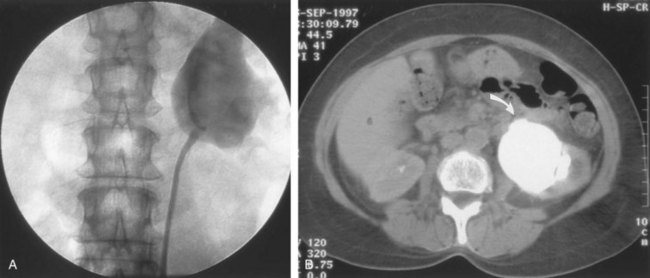

CT scan is frequently obtained for any patient presenting with acute flank pain (Fielding et al, 1997; Dalrymple et al, 1998; Vieweg et al, 1998) (Fig. 41–3). Moreover, CT scans provide detailed anatomic and functional information to aid in diagnosis of UPJ obstruction (Fig. 41–4A-C). Both ultrasonography and CT scanning also have a role in differentiating acquired causes of obstruction such as radiolucent calculi or urothelial tumors. In neonates and infants, the diagnosis of UPJ obstruction has generally been suggested either by routine performance of maternal ultrasonography or by the finding of a flank mass. In either setting, renal ultrasonography is usually the first radiographic study performed. Ideally, ultrasonography should be able to visualize dilatation of the collecting system to help differentiate UPJ obstruction from multicystic kidney and determine the level of obstruction. UPJ obstruction and multicystic kidneys are distinguishable in the majority of cases by ultrasound alone. With UPJ obstruction, the pelvis is visualized as a large, medial sonolucent area surrounded by smaller, rounded sonolucent structures representing dilated calyces. At times, dilated calyces will be seen connecting to the pelvis via dilated infundibula (Fig. 41–5).

Figure 41–3 Noncontrast CT scan performed as the initial radiographic study in a patient presenting with left flank pain revealed hydronephrosis to the level of the ureteropelvic junction (UPJ). No calculus was visualized, and a presumed diagnosis of UPJ obstruction was considered. This proved correct on subsequent radiographic studies.

Figure 41–4 A, Contrast-enhanced CT scan identifies a classic ureteropelvic junction (UPJ) appearance in early-phase imaging. B, Early images reveal normal nephrogram and delayed filling of the obstructed, dilated UPJ. C, Delayed images demonstrate holdup of contrast drainage on the right compared with the normal left side.

The indications to intervene for any patient with UPJ obstruction include the presence of symptoms, progressive or overall impairment of renal function, development of upper tract stones or infection, or, rarely, causal hypertension. Historically, a percutaneous approach for definitive management of UPJ obstruction was offered only to those patients undergoing percutaneous removal of associated stones or to those who had previously failed open pyeloplasty. However, encouraging results ultimately led many centers to offer percutaneous endopyelotomy as primary therapy for almost any patient with UPJ obstruction. Even with the acceptance of laparoscopic pyeloplasty, percutaneous endopyelotomy is also appropriate for those patients with UPJ obstruction and concomitant pyelocalyceal stones, which can then be managed simultaneously. Contraindications to a percutaneous endopyelotomy are similar to the contraindications to any endourologic approach and include a long segment (>2 cm) of obstruction, active infection, or untreated coagulopathy. Whereas the impact of crossing vessels is controversial, the mere presence of crossing vessels is not a contraindication to an endopyelotomy (Motola et al, 1993b; Nakada et al, 1998; Lam et al, 2003b). However, significant entanglement of the UPJ by crossing vessels can occasionally be identified and this may render any endourologic approach unsuccessful. When such entanglement is suggested by intravenous or retrograde pyelography (Fig. 41–7), it can be reliably verified using three-dimensional helical CT (Kumon et al, 1997).

Figure 41–9 A, Retrograde study in this patient with left ureteropelvic junction obstruction reveals a “high insertion” of the left ureter. B, CT scan in this same patient reveals the ureter inserting on the anatomically anterior aspect of the renal pelvis. A marsupializing incision must be made in a true posterior direction from the ureter into the renal pelvis.